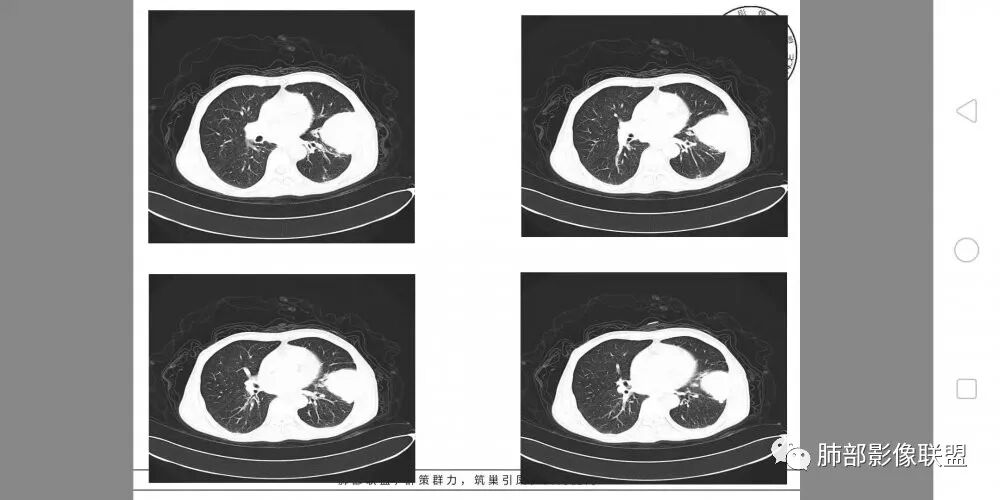

病灶与叶裂之间夹有上叶下舌段支气管、血管。舌段支气管后移,尖后段支气管前移,病灶将支气管撑开。

叶裂受压后移,提示病灶不来源于叶裂。

内朝外?外朝内?

支气管推移-----提示外朝内

近端肺动脉受压外移,但是有部分进入病灶内-------提示与肺有千丝万缕的关系。